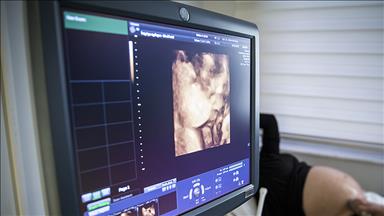

"Hastamız, ilk iki saat içerisinde başvurdu. MR filminde beyin sapı dediğimiz çok tehlikeli bölgede, kalp ve solunum merkezini besleyen atar damarda tıkanıklık olduğunu farkettik. Direkt tıkalı bölgeye girerek müdahaleyi yaptık ve hasta sağlığına kavuştu. Operasyonun ikinci gününde ise ayakta taburcu ettik. Beyni besleyen büyük damar tıkanıklıkları müdahale edilerek açılabiliyor. Fakat beyinde kalp ve solunum merkezini besleyen 'PICA' adını verdiğimiz damara müdahale yapılamamıştı. Çünkü bu damar küçük, teknik olarak tıkanıklığı tesbit etmek çok zor. Bu ameliyatı dünyada ilk, ülkemizde ve üniversitemizde yapmış olduk. Şu anda literatürde bu vakanın örneği yok."

Beynin küçük damarına kritik müdahale